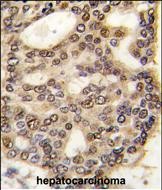

- Formalin-fixed and paraffin-embedded human hepatocarcinoma tissue reacted with HDGF antibody (C-term) (Cat.#P30262), which was peroxidase-conjugated to the secondary antibody, followed by DAB staining. This data demonstrates the use of this antibody for immunohistochemistry; clinical relevance has not been evaluated.